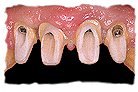

A continuación podrá ver algún tipo de prótesis sobre

implantes:

Antes y después del

tratamiento.